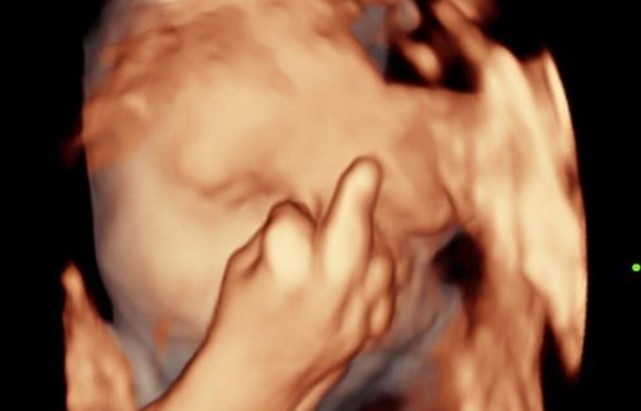

Neverovatna slika koja je šokirala svet, Foto: Kennedy News and Media

A onda se dogodio neviđen šok! Videli su bebinu ručicu ali i srednji prst koji im je pokazala!

“Kao da je želela da nam poruči da je ne gledamo i da je ostavimo da odmara. Ne znam kako da drugačije protumačim ovaj presmešan, ali i pomalo zabrinjavajući njen gest. Valjda nam neće praviti problema u životu posle. Pitam se zašto se ovo baš meni moralo dogoditi”, rekla je buduća majka.

“Nije ovo ništa neobično. Bebe se protežu u stomaku, svašta rade. Šutiraće te vremenom, tako da je ovaj srednji prst samo uvod”, glasio je jedan od komentara.